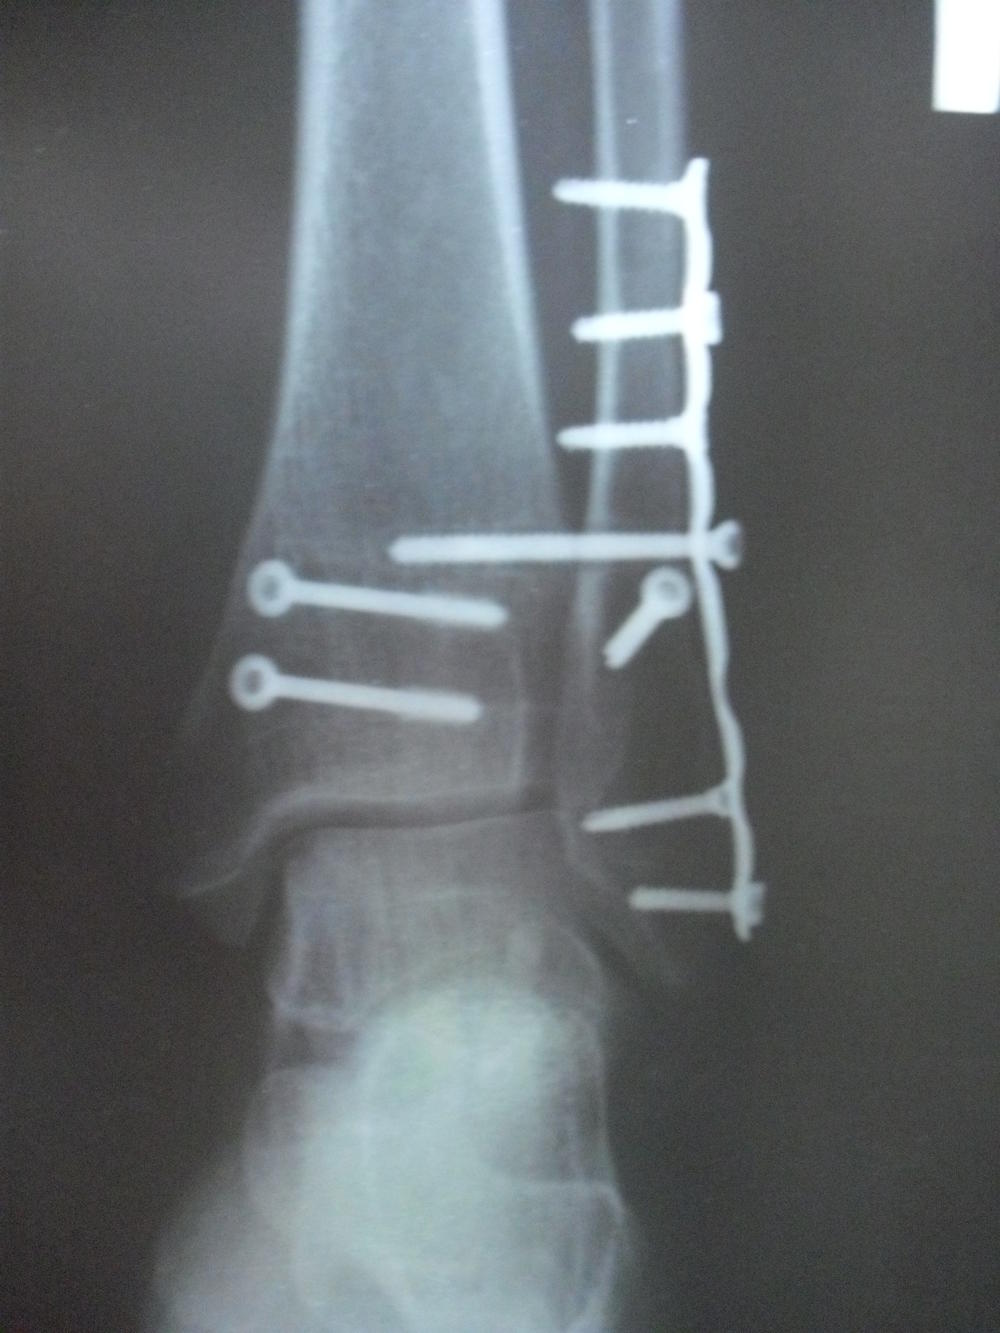

Девочки ну и немного расскажу о последних событиях,я недавно перенесла повторную операцию-вытащили мне все болты и пластину и я наконец-то первый раз на руки снимок ноги получила-честно в ужасе была-что там было!!!Счас уже ничего этого нет!Слабонервных просьба не смотреть!!!)))

Да,уж сама как увидела чуть по стеночке не сползла-не думала что там такое,раньше мне видимо врачи снимки боялись показывать.А болт сломанный был один,это тот что самый длинный-его тяжелее всего удалять пришлост-СПАСИБО ОГРОМНОЕ врачам института имени Вредена!!!!золотые руки у них!!!